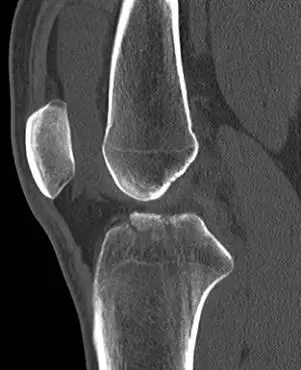

20歲男性病人因打球摔傷,膝部疼痛接受電腦斷層檢查,發現脛骨近端有骨折如圖。最可能合併下列何者傷害? 圖片描述 圖片描述

此題核心在於認識「Tibial eminence fracture(脛骨脊骨折)」即是前十字韌帶(ACL)於脛骨脊附著處之骨骼撕脫,為兒童與青少年特有的ACL等價損傷。

• 由矢狀面CT可見近端脛骨內、外側平台之間出現一塊線性骨片向前方偏移,骨片與平台底部仍以細小纖維連續,呈現典型的骨脊撕脫片段。

• 冠狀面CT顯示該撕脫片位於脛骨平台中央、略微向前凸出,並與髁間區保持一鉸鏈樣連接。

• 無明顯平台塌陷或關節面大範圍粉碎,提示為關節內骨折但屬撕脫型態。

本例為典型Tibial eminence avulsion fracture,專屬於ACL在脛骨脊附著處之骨撕脫。青少年運動傷害以韌帶附著處骨骼未完全骨化而先行撕脫最為常見。CT影像顯示中央部骨片向前偏移,正好吻合ACL撕脫機制;其他韌帶附著位置與本影像不符,故最佳選擇為前十字韌帶(ACL)合併損傷。